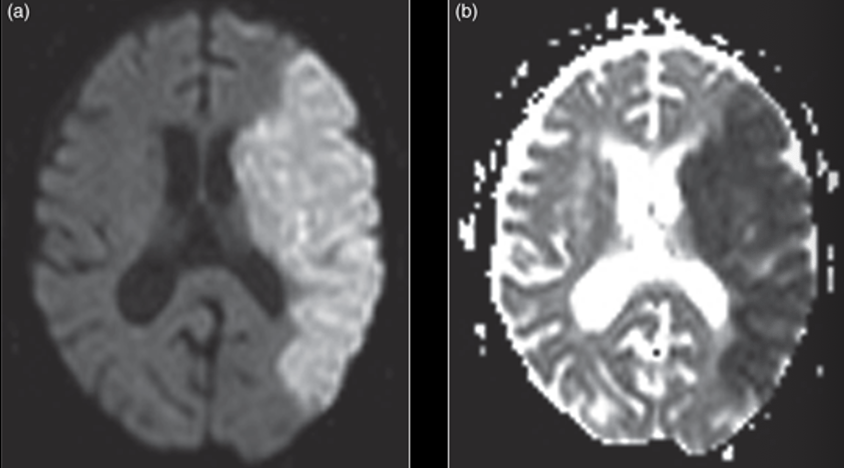

Watershed stroke looks like ______ on imaging

linear pattern